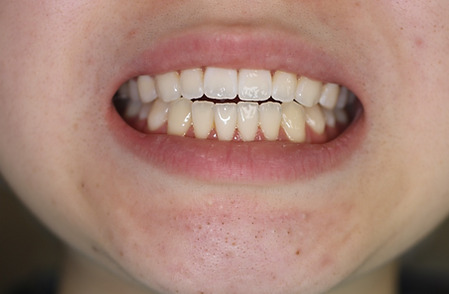

2ホワイトニング【治療例1】

治療前

治療後